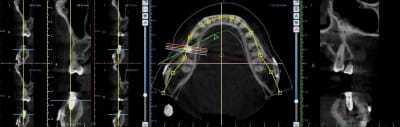

A moins que j'aie mal lu, personne pour parler des plaques de fixation en titane.

Sont elles dues a un LEFORT III ou un accident (je pense plutot au premier cas, symétrie assez parfaite).

Hypothese: pendant longtemps on peut avoir un os assez peunspongieux, peu vascularisé en aval des plaques. Est ce que cette mobilité bizarre de la 7 qui normalement n'aurait pas du moufter (!) et le rejet implantaire ne sont pas dus a ca?

Bien vu.

Les implanto qui ont déjà déposé ce genre de matériau trouvent souvent un os "bizarre" quand l'implant est à proximité (2 cas rapportés par des potes)

Le verdict ce matin au CBCT... Trop vestibulé (classique) même si mon axe d'émergence sort bien au niveau de la cuspide palatine maxillaire, sous forage et nécrose par compression en essayant de le tanker à la main. Dans du D1 vous avez une alternative cylindrique dans vos tiroirs ou vous restez sur du cylindro-conique ? Dépose programmée. Pour la pulpectomie de 47, je vais attendre un peu. 8 semaines vous semble raisonnable pour réimplanter ? Quels sont vos conseils pour la réintervention ? Merci à tous

clairement ton image de CBCT me fait plutôt penser à un pb d'échauffement

peut être en plus augmenté par la compression générée par le design de ton implant, très classique avec le CC parce que c'est pas un implant auto taraudant, il est fait pour être compressif...

Compression lors de la pose, c’est sûr. Trop vestibulaire, aussi. Échauffement lors du forage, en général la douleur est plus rapide, plutôt 2-3 jours après la pose.

En revanche, c’est l’énorme image apicale à l’implant qui m’étonne. Tu as le CBCT, préopératoire ?

Elle a bien subit une osteotomie pour de l'orthognatique mais cela date de 1994 ...